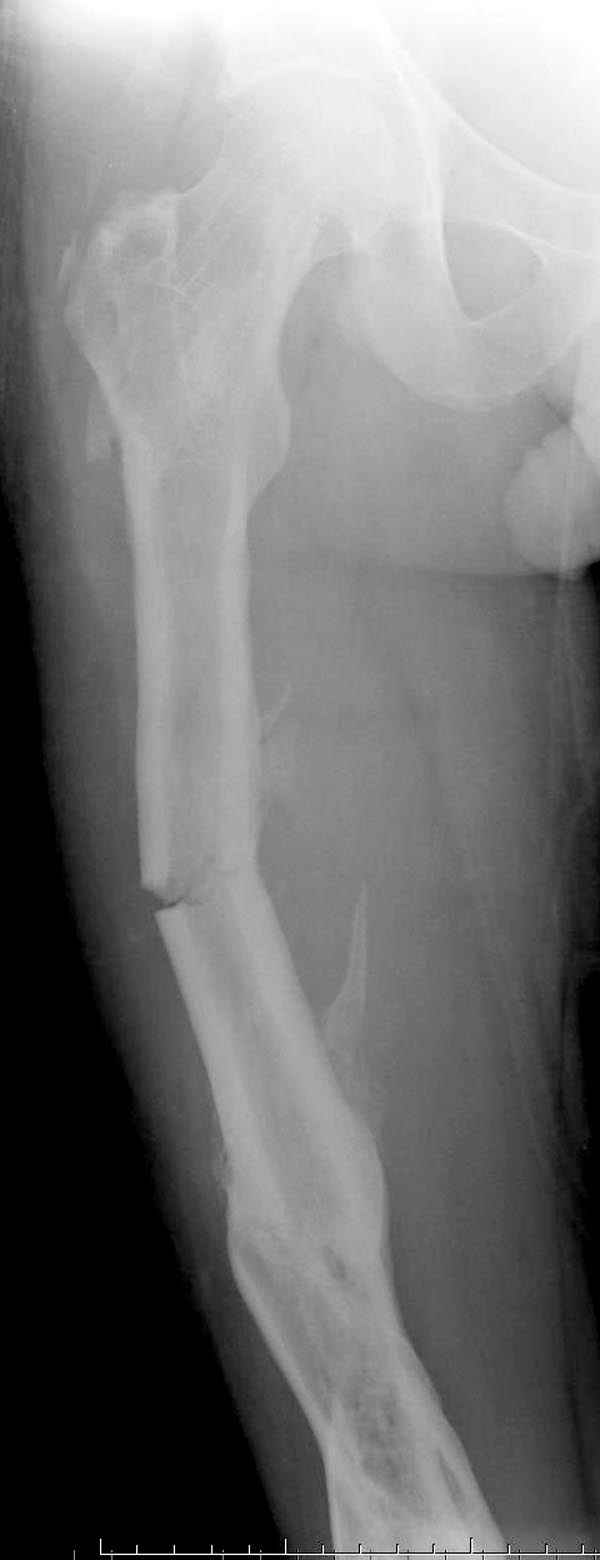

Представляю снимки больного с политравмой: леченного в другом мед.учреждении по поводу открытого перелома бедра, сперва аппаратом наружной фиксации, затем пластиной. Обратился к нам через 8 месяцев после удаления пластины с проблемой несросщего перелома бедренной кости, без клинических проявлении к инфицированию (не все снимки сохранены)

Рутинный интрамедуллярный остеосинтез с расверливанием и с фиксацией реконструктивным трокантерик штифтом (рис №1, №2),

При обзоре причин перелома, на снимке №2 обнаружили, что один из стержней аппарата наружной фиксации проходил только через передний кортекальный слой, что создало стрессовую зону на бедре и в результате перелом из-за незначительной травмы.